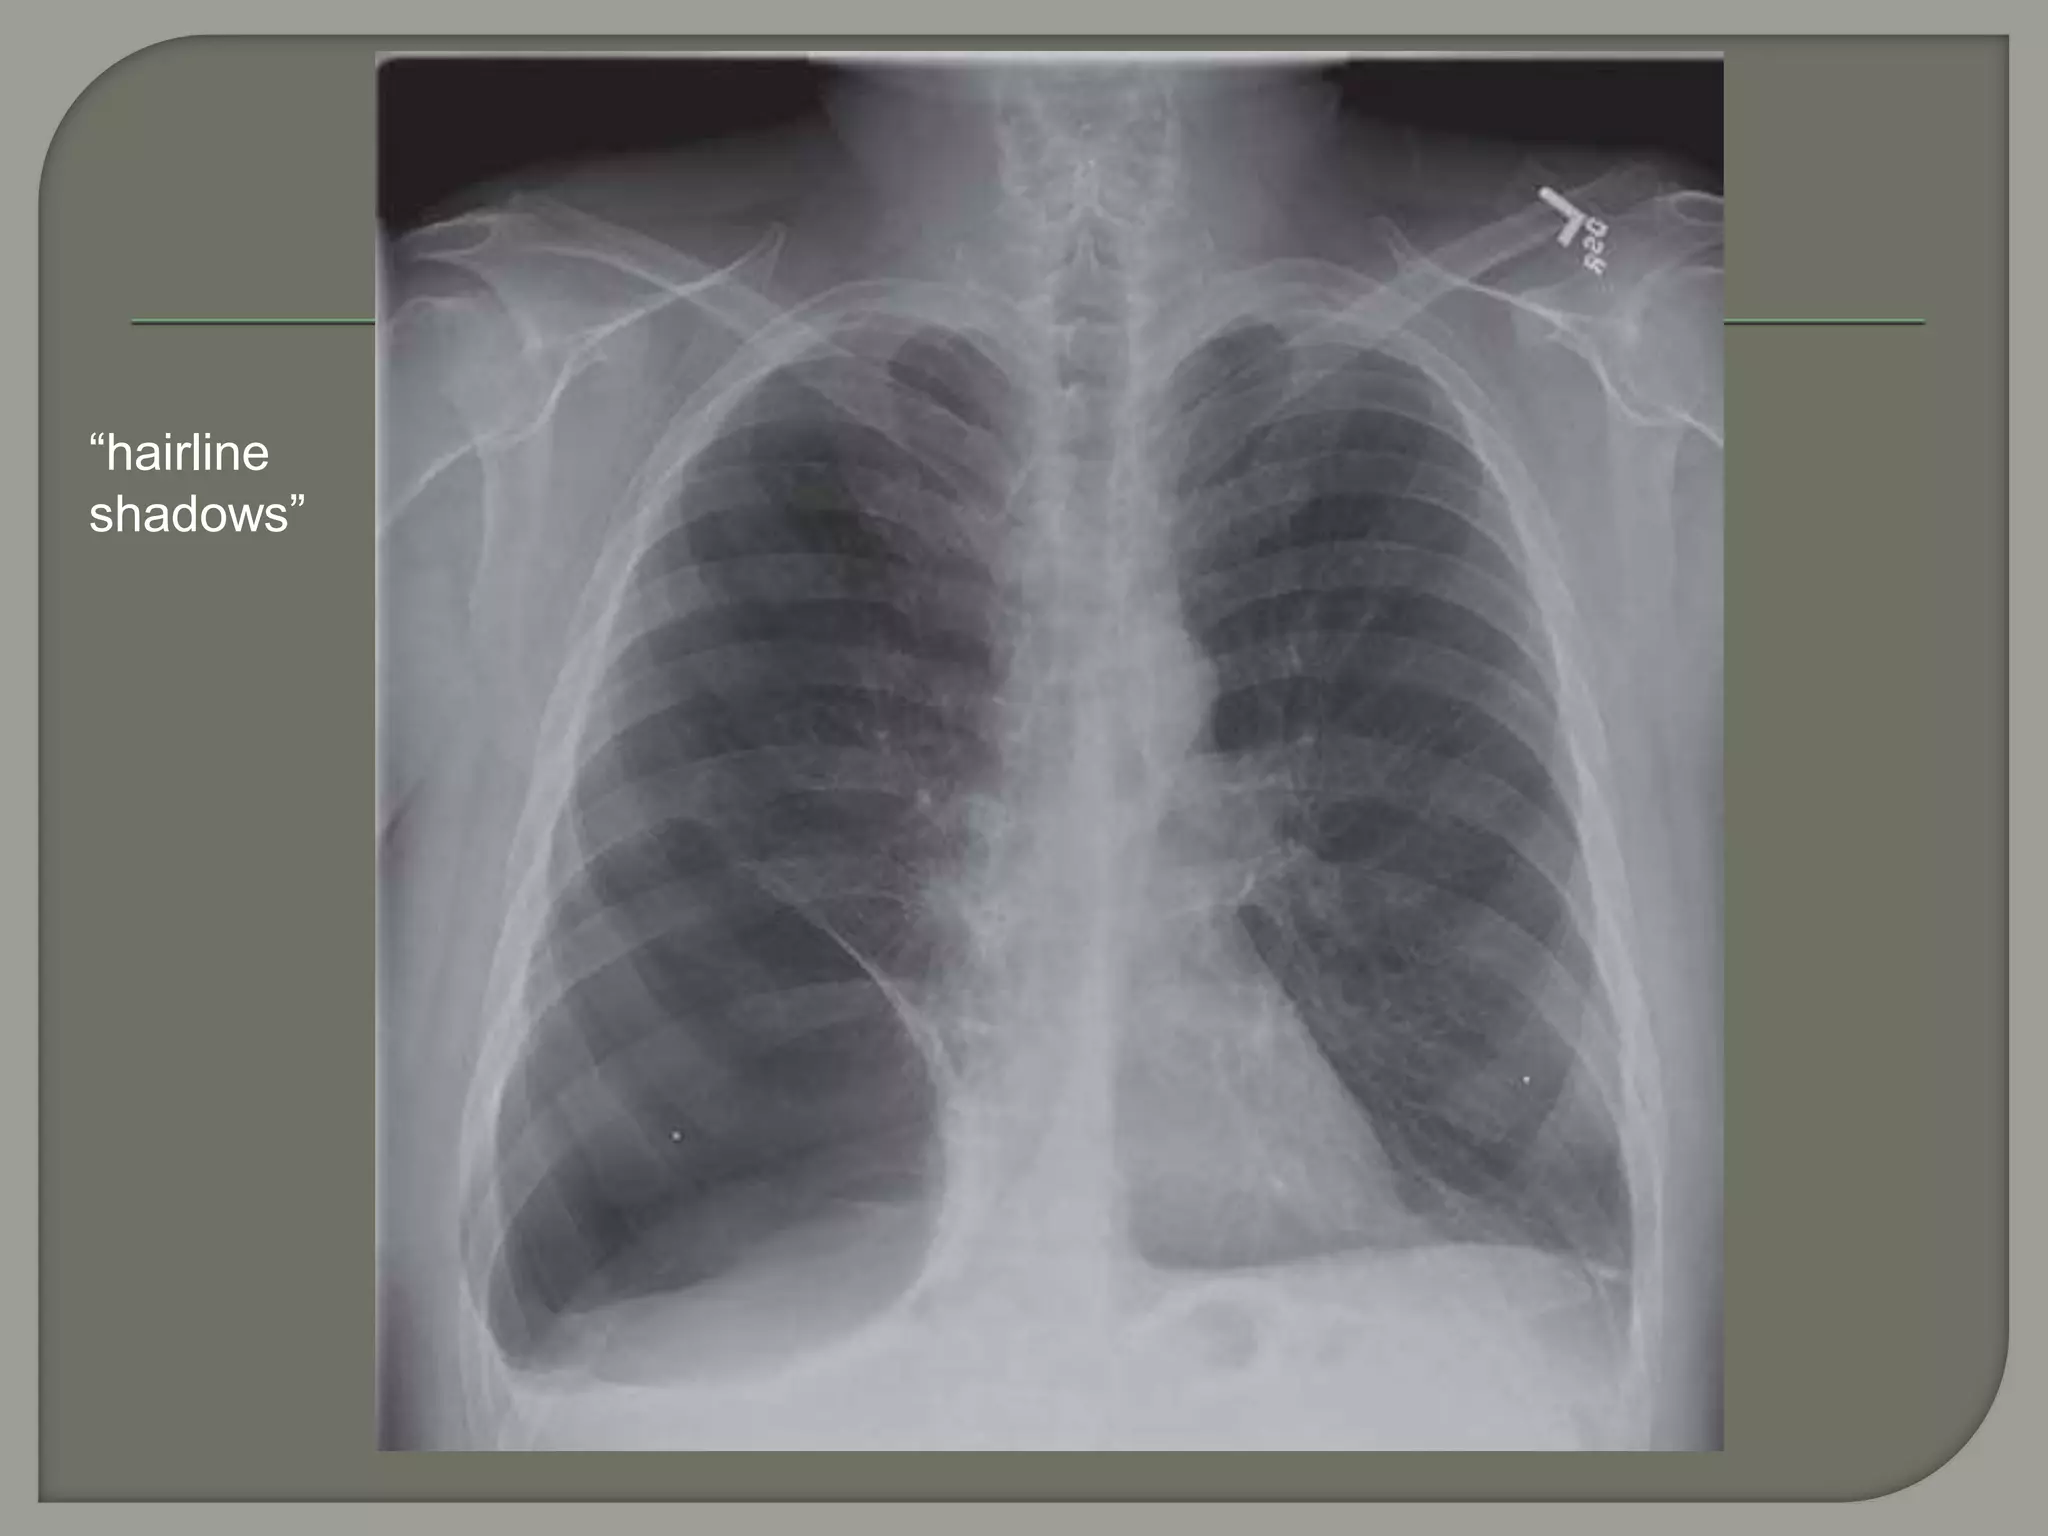

“hairline

shadows”